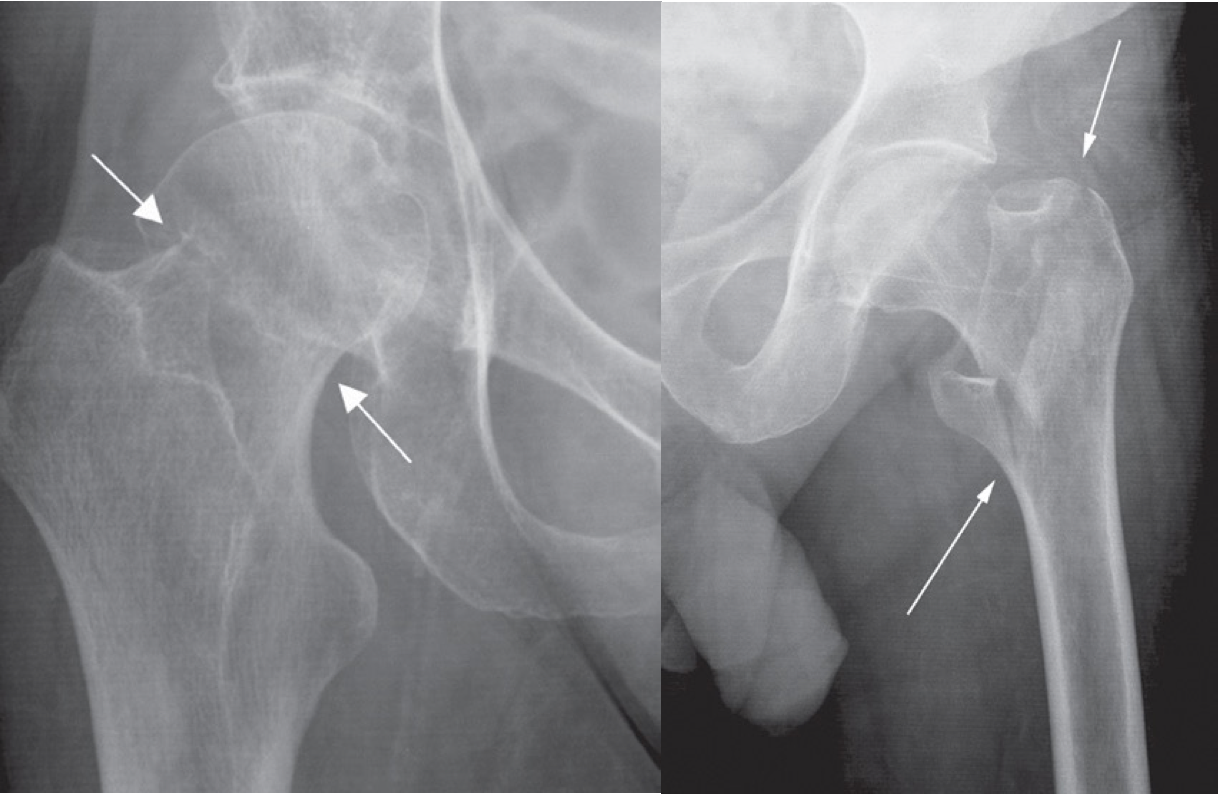

A. Impacted femoral neck fracture (arrows) causing only a sclerotic line and disruption of the trabecular architecture. z

B. Intertrochanteric fracture (arrows) between the greater and lesser trochanters.